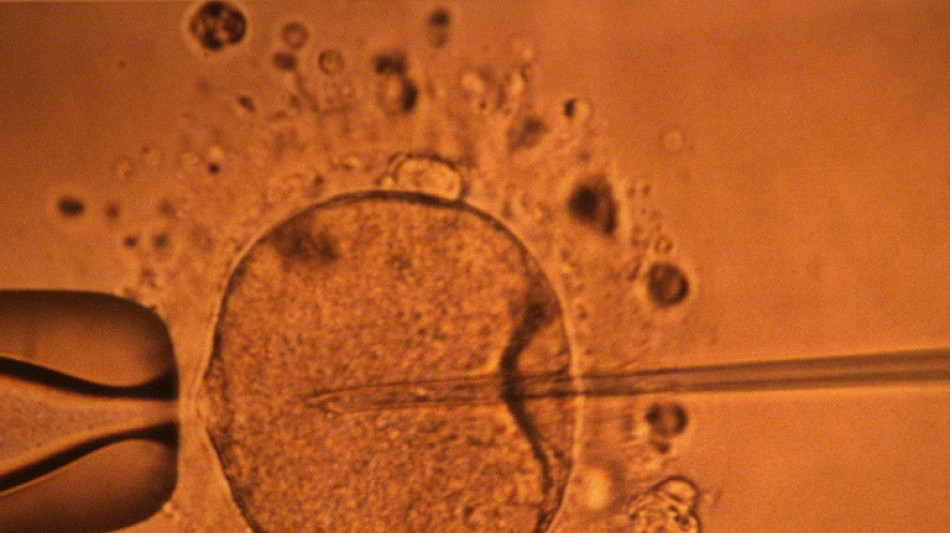

La concentration en spermatozoïdes, l'un des facteurs de la fertilité masculine, a nettement baissé à travers toute la planète au cours des dernières décennies, avance une vaste étude publiée mardi.

"La concentration en spermatozoïdes a sensiblement diminué entre 1973 et 2018", résument les auteurs de ce travail, paru dans la revue Human Reproduction Update et réalisé en compilant une quarantaine d'études préalables.